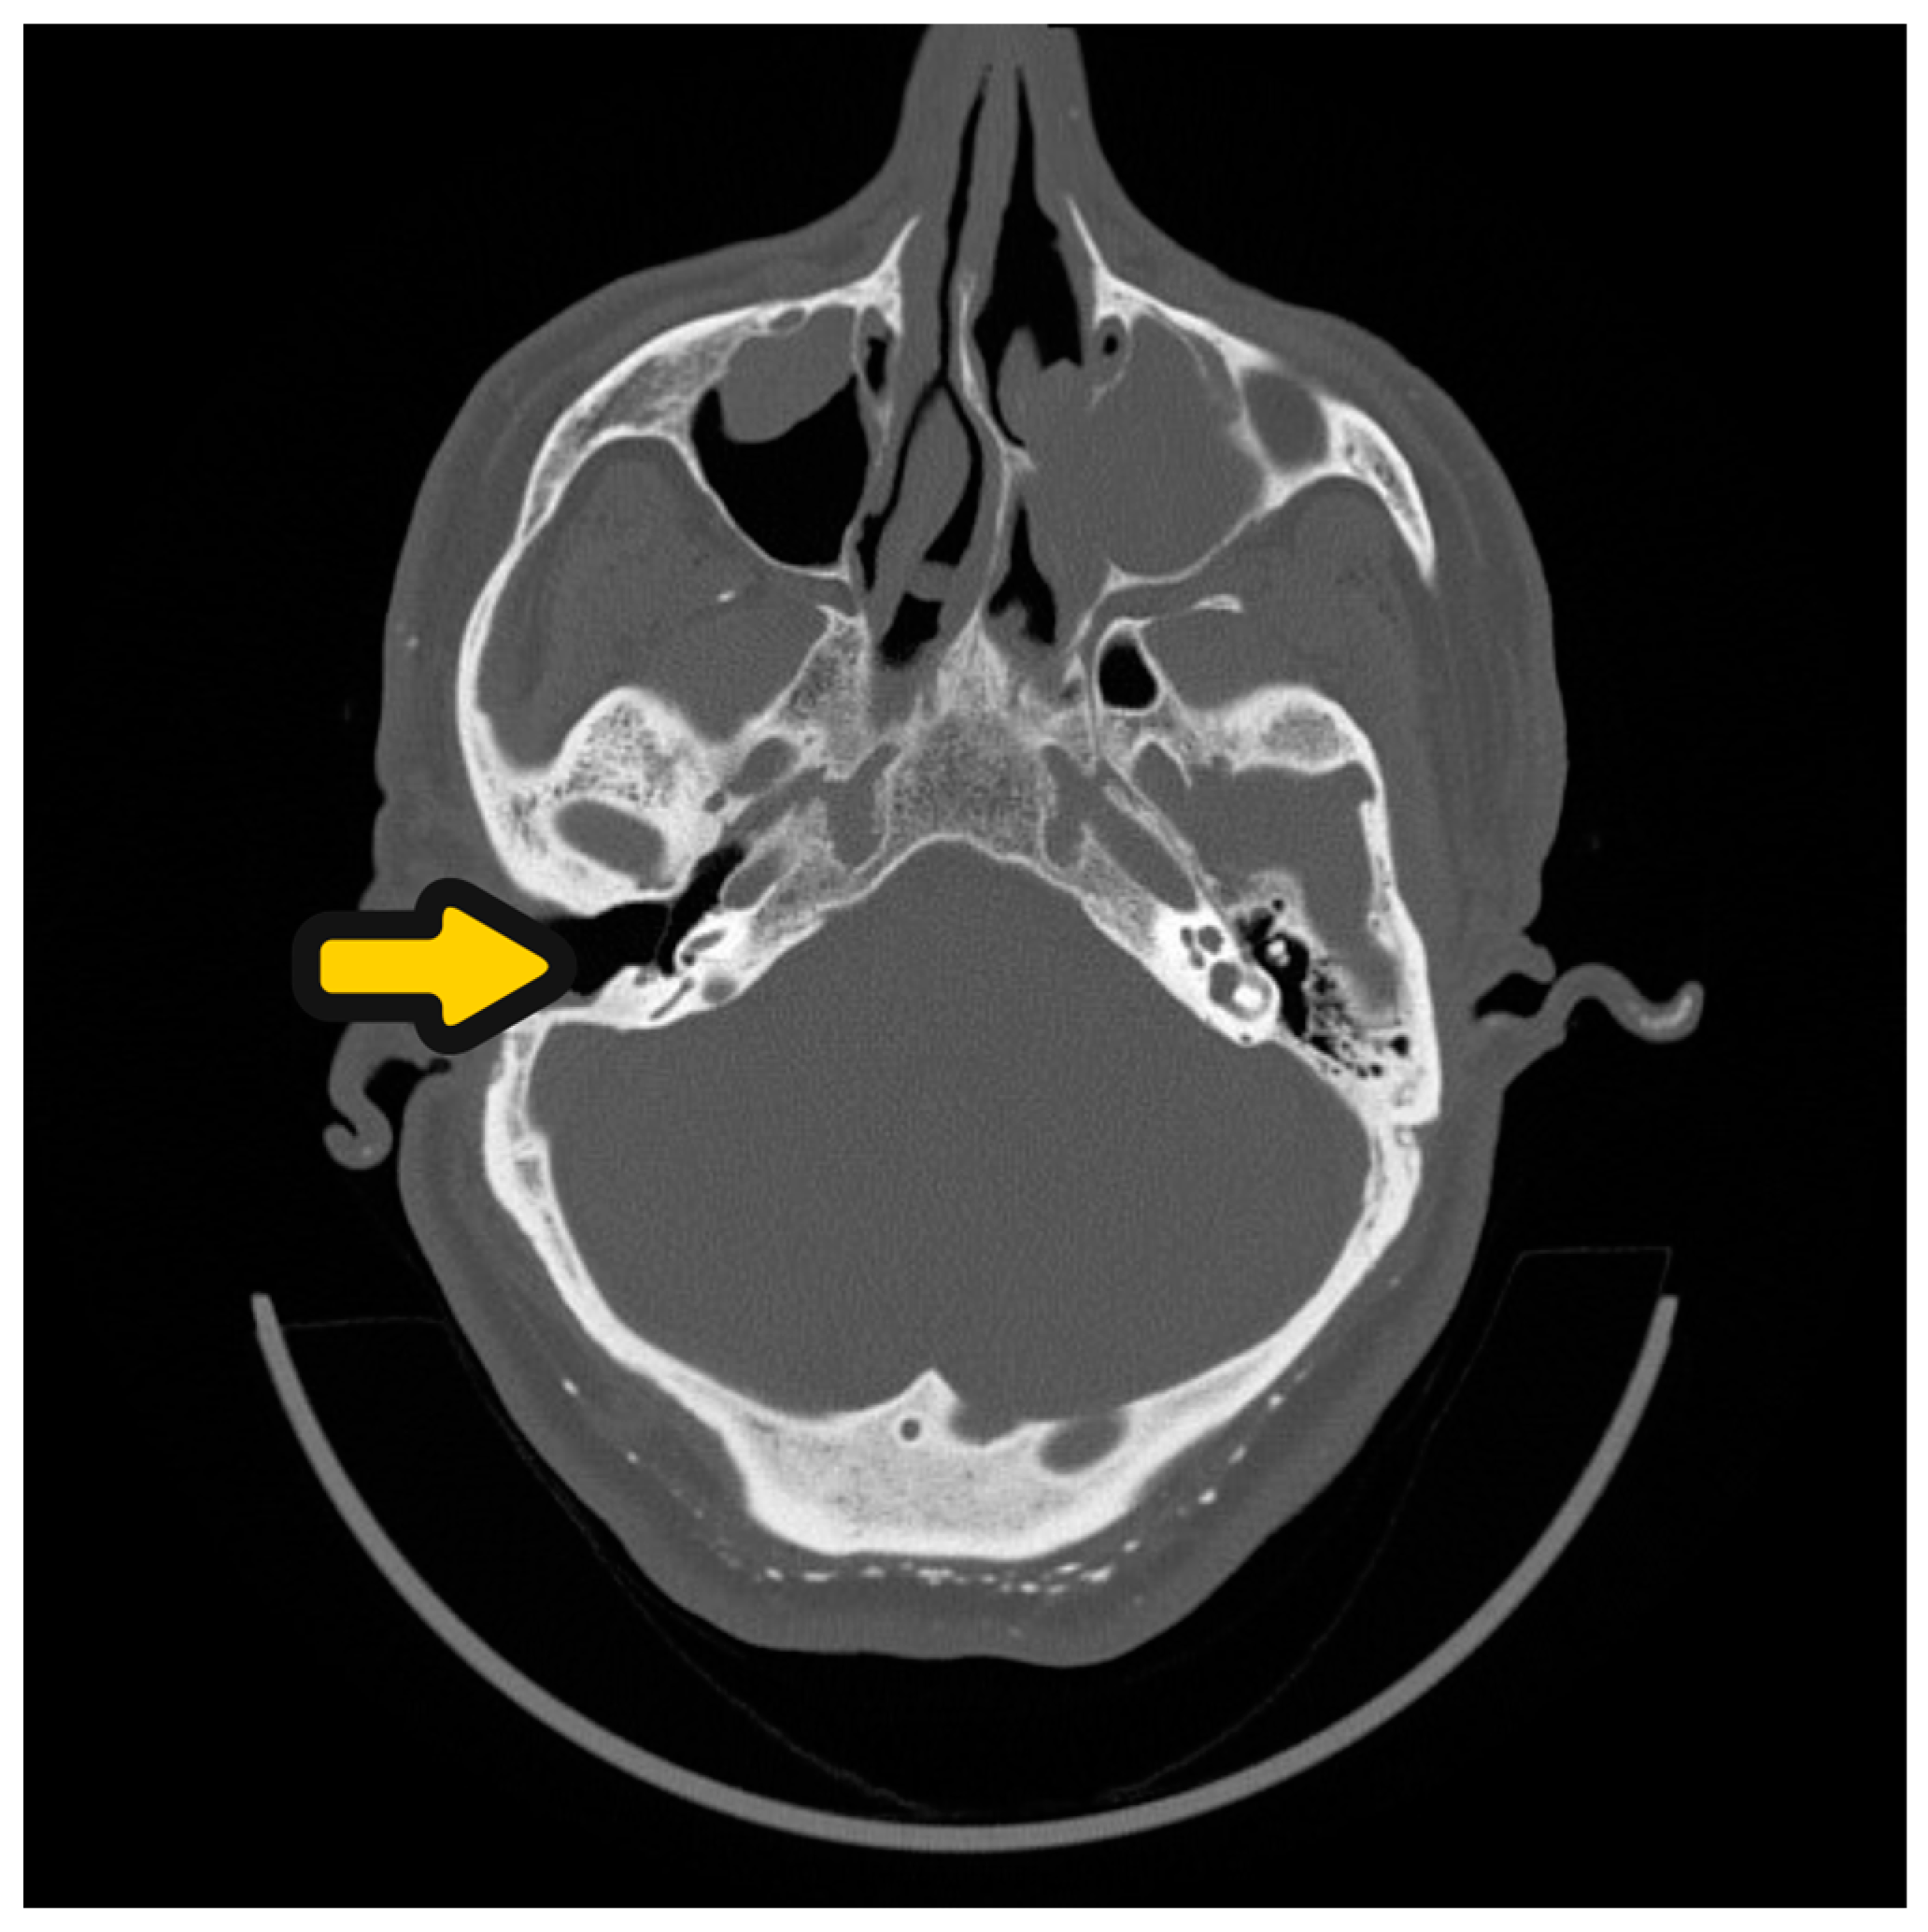

3.2. Case 2